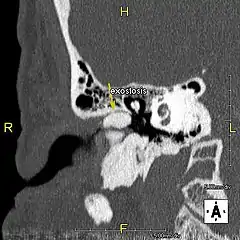

Exostose du surfeur

L'exostose du surfeur ou oreille de surfeur est une exostose, c'est-à-dire une croissance osseuse anormale, qui pousse vers l'intérieur du conduit auditif[1]. L'os entourant le conduit auditif réagit à l'agression thermique et mécanique de l'eau froide et de ses turbulences, par une nouvelle croissance osseuse qui a pour effet de resserrer le conduit auditif.